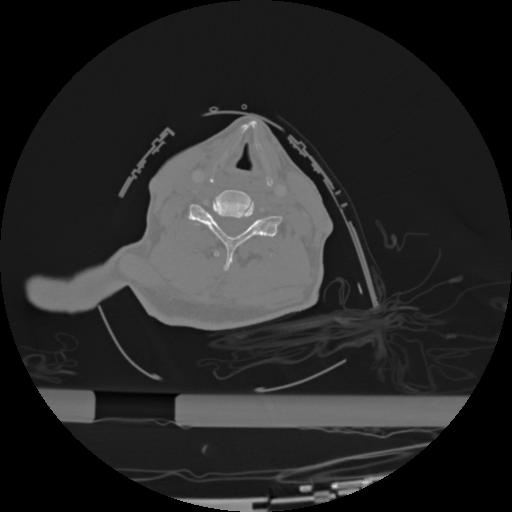

22 ANGIO,CE,Vol,0.5,ANGIO,,